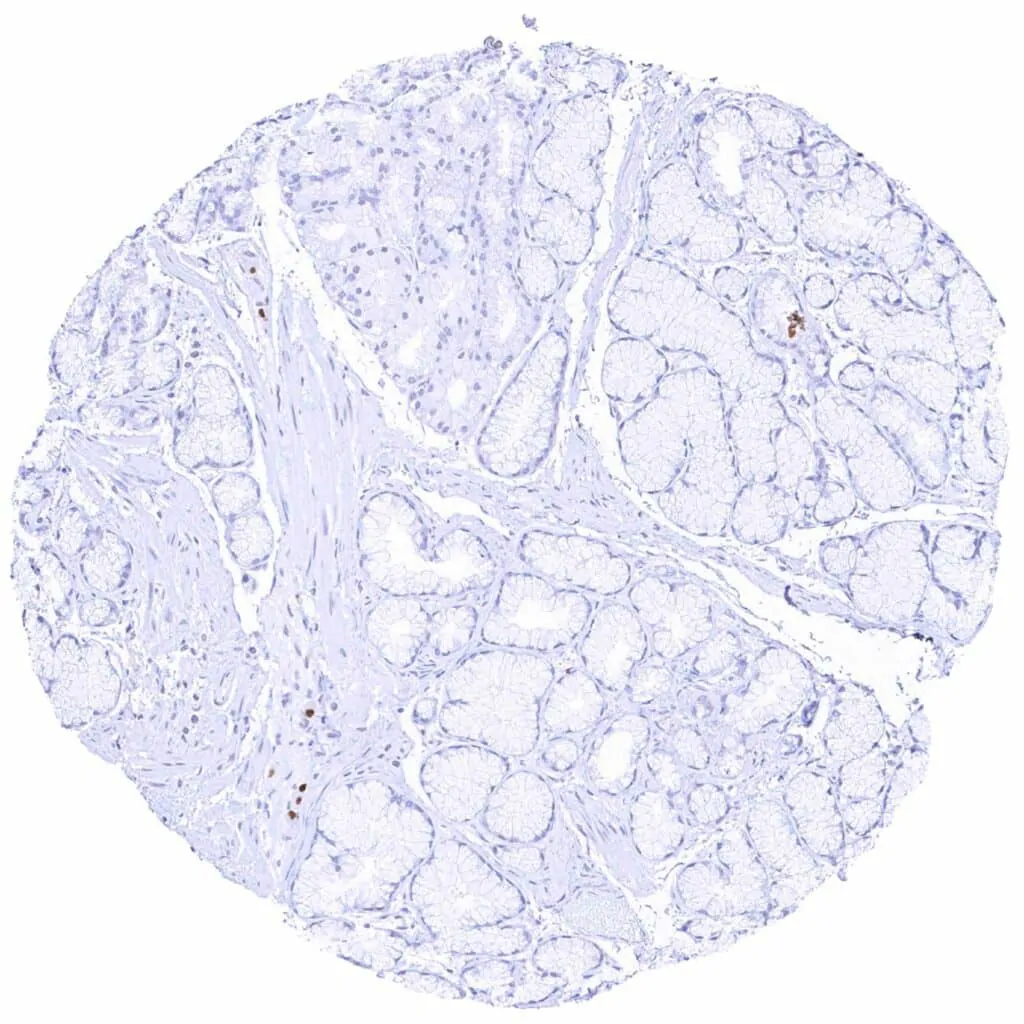

Pancreas